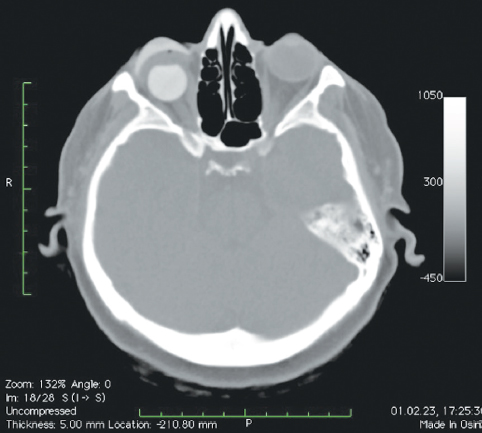

Рис. 9. Пациент, 57 лет. 3 года после операции с имплантацией эндопротеза с изменённой геометрией, дефект передней поверхности культи, обнажение края имплантата. МСКТ-исследование

Fig. 9. Patient, 57 y. o. 3 years after surgery with implantation of an endoprosthesis with modified geometry. Defect of the anterior surface of the stump, exposure of the orbital implant

В мягких тканях вокруг изменённых имплантированных сфер нами выявлены уплотнения, без признаков кальцинации и деструкции стенок орбиты (рис. 7, 8). Кроме того, у одной пациентки было отмечено не только изменение геометрии сферы в виде срезанной части (рис. 10, а), но и наличие множества фрагментов полимерного материала идентичной рентгенологической плотности. Эти фрагменты имплантата находились за задним полюсом полимерного вкладыша в мягких тканях до вершины орбиты (рис. 10, b).